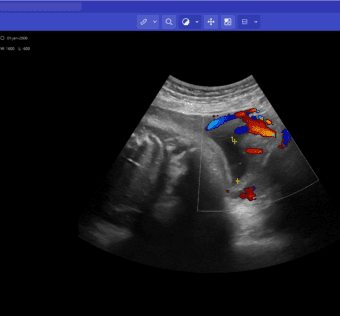

![]() | What You Should Know:– Today Truveta announced the availability of expanded concepts from clinical notes — including family history, medication details reported to providers, and complex concepts for a wide range of therapeutic areas... #TruvetaExpandsEHRDataAccess Truveta, a healthcare data platform, is enhancing electronic health record (EHR) data access by incorporating complex medical concepts and millions of images into its system. This expansion will provide healthcare IT professionals with a more comprehensive view of patient health information, enabling better decision-making and personalized care. #HealthcareDataPlatform#EnhancedEHRDataAccess By integrating complex medical concepts and a vast collection of images, Truveta is revolutionizing EHR data access. This enhancement will allow healthcare IT professionals to delve deeper into patient records, gaining insights that were previously inaccessible. #MedicalConcepts #ImageIntegration#ImprovedDecisionMaking The incorporation of complex medical concepts and images in E As a healthcare IT expert, write a 50-80 extractive summarization summary for social media platforms, that is focused, accurate, and strictly reflects the content based on a blog post from the given URL. The summary should include all headings from the blog post, with inline hashtags for each heading. When including the inline hashtags, use specific hashtags related to the headings rather than generic healthcare or technology hashtags. If the headings in the blog post are too long or unclear, feel free to rephrase them into shorter, clearer versions that still convey the main idea. The target audience is other healthcare IT professionals.Following is the title and url. Truveta Expands EHR Data Access with Complex Concepts & Millions of Images https://hitconsultant.net/2024/05/03/truveta-expands-ehr-data-access-with-complex-concepts-millions-of-images/ { "id": "chatcmpl-9KpJCXxS1g6zMJGfNBEEd2Uny7ygX", "object": "chat.completion", "created": 1714750818, "model": "gpt-3.5-turbo-0125", "choices": [ { "index": 0, "message": { "role": "assistant", "content": "#TruvetaExpandsEHRDataAccessnTruveta, a healthcare data platform, is enhancing electronic health record (EHR) data access by incorporating complex medical concepts and millions of images into its system. This expansion will provide healthcare IT professionals with a more comprehensive view of patient health information, enabling better decision-making and personalized care. #HealthcareDataPlatformnn#EnhancedEHRDataAccessnBy integrating complex medical concepts and a vast collection of images, Truveta is revolutionizing EHR data access. This enhancement will allow healthcare IT professionals to delve deeper into patient records, gaining insights that were previously inaccessible. #MedicalConcepts #ImageIntegrationnn#ImprovedDecisionMakingnThe incorporation of complex medical concepts and images in E" }, "logprobs": null, "finish_reason": "length" } ], "usage": { "prompt_tokens": 187, "completion_tokens": 150, "total_tokens": 337 }, "system_fingerprint": "fp_a450710239" } Prompt Tokens - 187 |